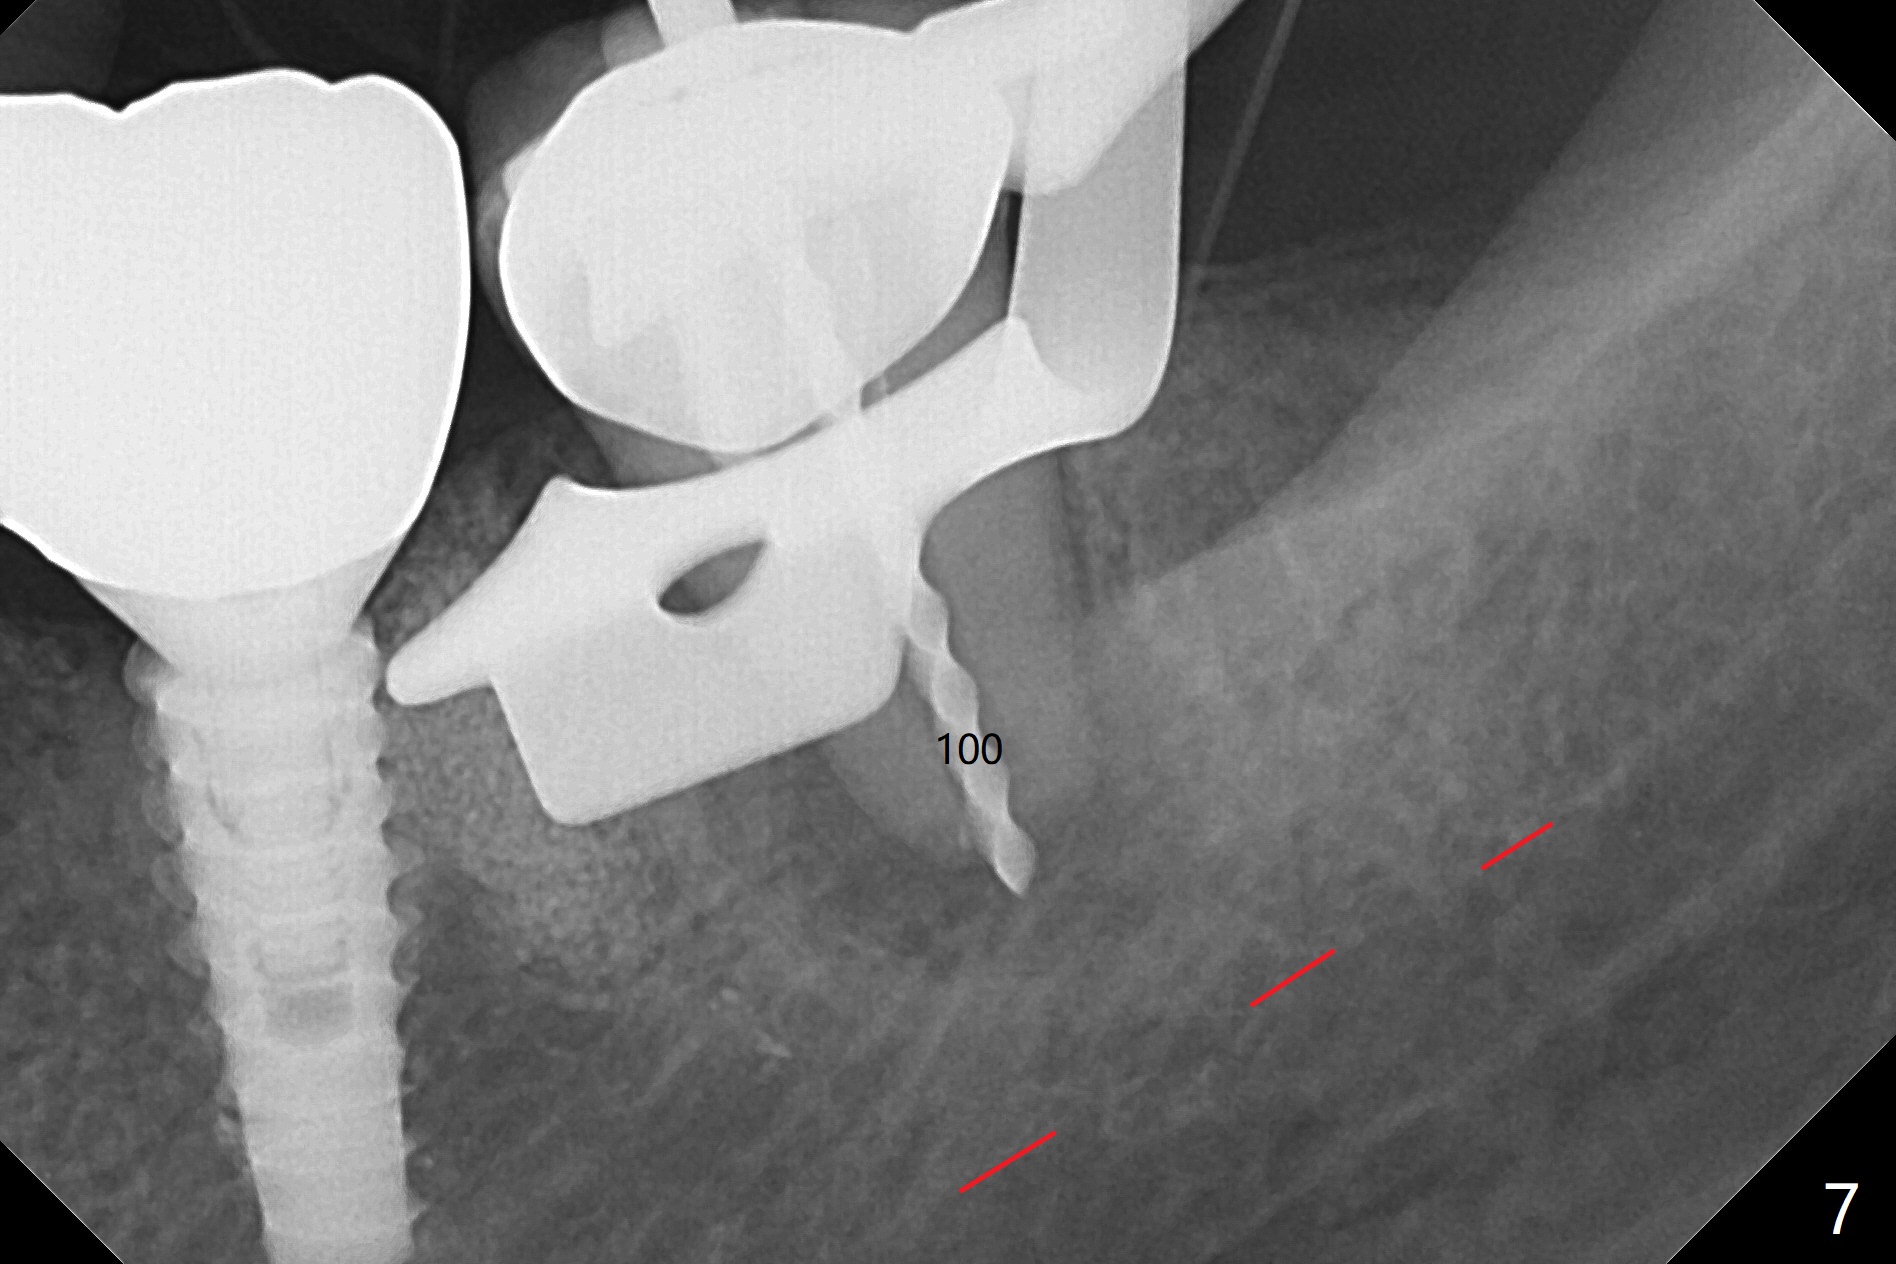

After making a 10 mm incision at the site of #19, #15c blade is used as an osteotome to start bone expansion, followed by Magic Split and Magic Expander (ME, 3 mm in diameter).  The depth is approximately the bottom of the mesial socket.  The osteotomy beyond the socket has to be done with 1.6 mm pilot drill (Fig.1) in combination of ME.  Following ME 4.3 mm and Magic Drill (MD) 3.8 mm for 15 mm (gingival level), a 4.5x11 mm dummy implant is placed with 50 Ncm (Fig.3); the implant looks narrow for the edentulous space.  After ME 4.8, MD 4.3 for 13 mm and Final Drill for 15 mm, a 5x11 mm IBS is inserted with >50 Ncm (Fig.3).  With 2 more turns of the implant, a 6.5x4(2) mm abutment is placed (Fig.4).  Periodontal dressing is applied around the abutment for additional retention.  A provisional is fabricated 3 weeks postop.  The provisional and abutment are loose 4 months postop (Fig.5).  After retightening the abutment, impression is taken for final restoration.  There is no bone loss 1 year 3 months post cementation (Fig.6).  After use of #100 file (Fig.7), the canal is debrided with #140 file with 1.5 mm shorter in working length with placement of Calcium Hydroxide paste.  Pain gets worse post RCT retreatment. There is limited native bone for primary stability when an immediate implant is placed (red dashed line: the superior border of the Inferior Alveolar Canal).  Prepare IS regular and extra wide kits and tissue-level implants (>5 mm).  Socket preservation may be done instead.  If the socket is large and the vein is not so small, prepare PRF.  In fact blood drawing fails.  When the tooth is extracted, it is sensitive to remove granulation tissue.  Socket preservation is done with Vanilla graft at #18 (Fig.8); there is ~3.5 mm bone between the bottom of the single socket and the Inferior Alveolar Canal (red dashed line).  The socket at #18 seems to have healed 4 months post extraction (Fig.19), but the bone height appears to have been reduced (compare Fig.10,11).  The buccolingual width is also decreased (Fig.12,13).  A 4.5 or 5.0x10 mm implant is appropriate for the site (Fig.14).  There is no bone loss at #19 (which may be associated with the bone expansion) 1.5 years post cementation (Fig.15).  Therefore the osteotomy at #18 will be assisted with bone expanders after 2.2 mm drill.